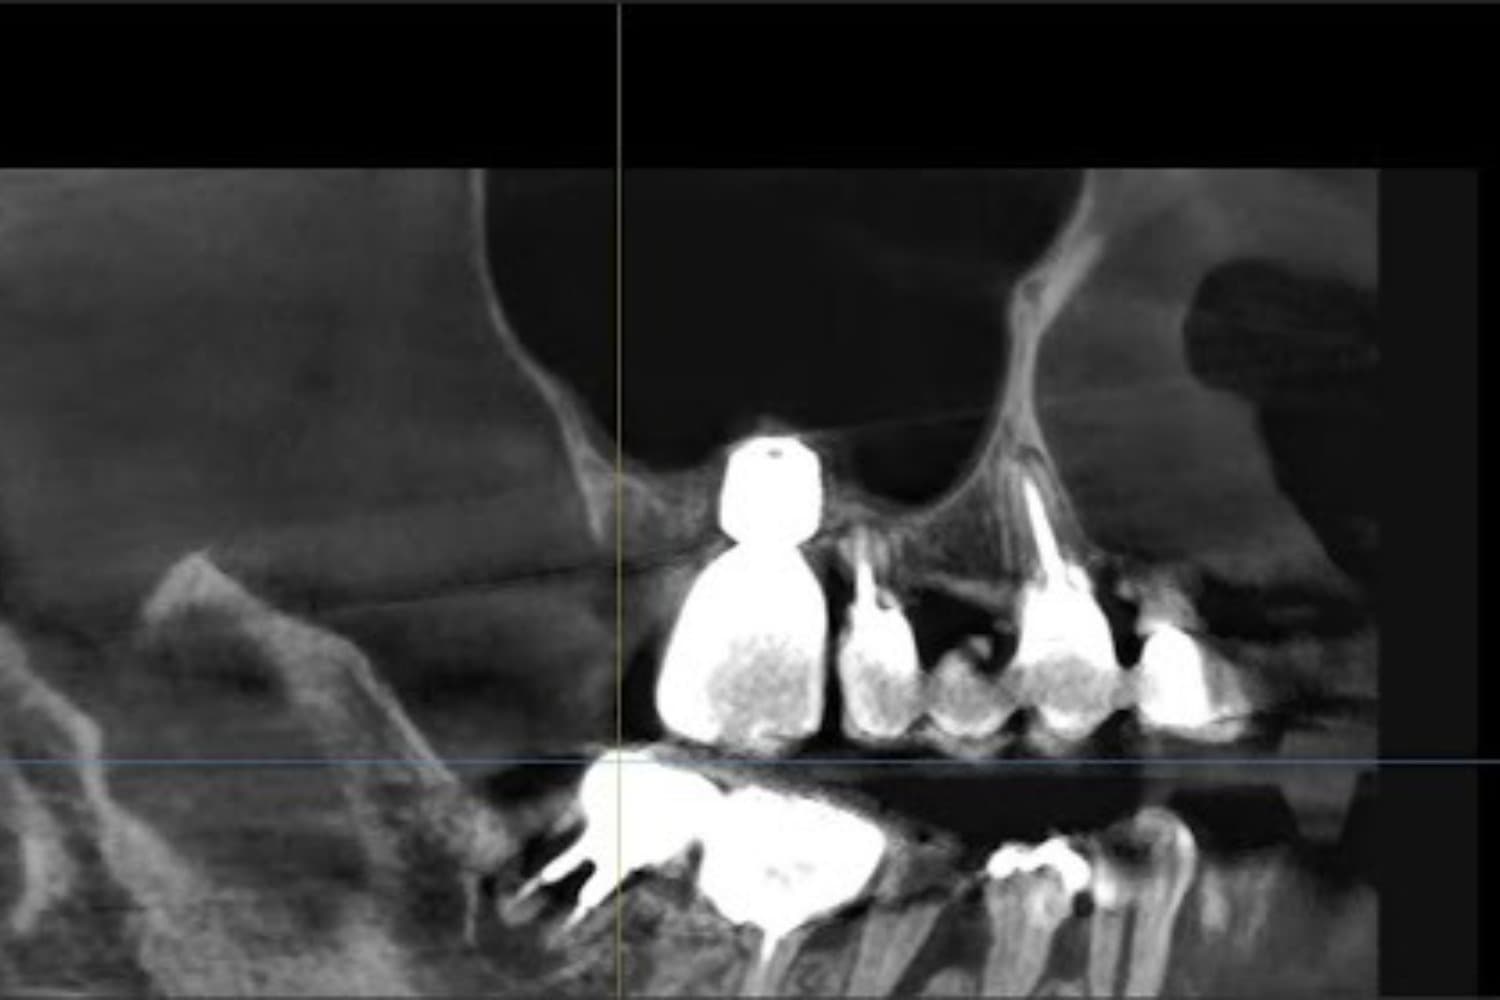

左上の歯のインプラント治療(40代女性)

Before

After

抜歯をおこない上顎洞内及び歯抜した周囲組織の回復を試みたあと、グラフトレスサイナスリフト・人口骨補填をともなうインプラント治療

50代

女性

主訴

左上の歯が歯根破折を起こしていた。何もしていなくとも痛みを感じる。

2ヵ月半

6回

368,500円(税込) 費用の内訳: 【インプラント基本料】330000円(税込み) 基本料金に以下を含む ・フィックスチャー及び手術費用 ・投薬費用、 ・レントゲン費用 ・インプラント上部費用(アバットメントおよびジルコニアクラウンの費用用) 【オプション費用】 ・グラフトレスサイナスリフト費用+人工骨費用 38500円(税込み)

・手術後に痛み・腫れ・出血・合併症等を引き起こす恐れがあります。 ・噛む感覚がご自身の歯と異なることがあります。 ・見た目がご自身の歯と異なる場合があります。 ・手術後もメインテナンスを続けないと、インプラントが抜け落ちてしまう恐れがあります。